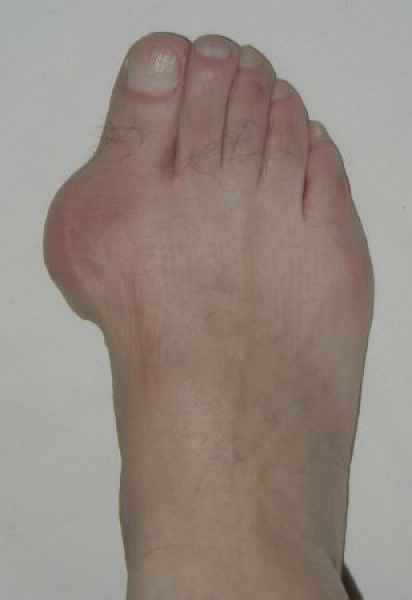

La marcha no solo es característica de la especie humana sino también de cada persona, y más aún varía según el estado de ánimo del momento. Una patología en los pies, se traduce en el rostro, en el ánimo, en el psiquismo. No sólo el dolor produce estos efectos, también un pie deformado o poco estético. En nuestra sociedad, la estética constituye un valor muy apreciado y estas alteraciones causan vergüenza fundamentalmente en las mujeres, que esconden en la playa sus pies en la arena y no pueden usar calzados elegantes.